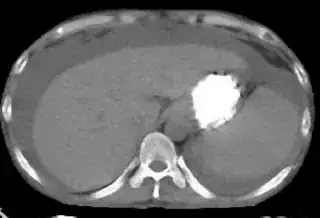

I am struggling in segmentation of images in matlab. My goal is to extract liver from ct scan images. This is sample image.

My problem is when I change image , rgb value of liver section may be different. Here is other sample image

Sample image 2.

For this image rgb value vary from 160 to 190 for each color component (r, g & b). Please help me to solve the problem.